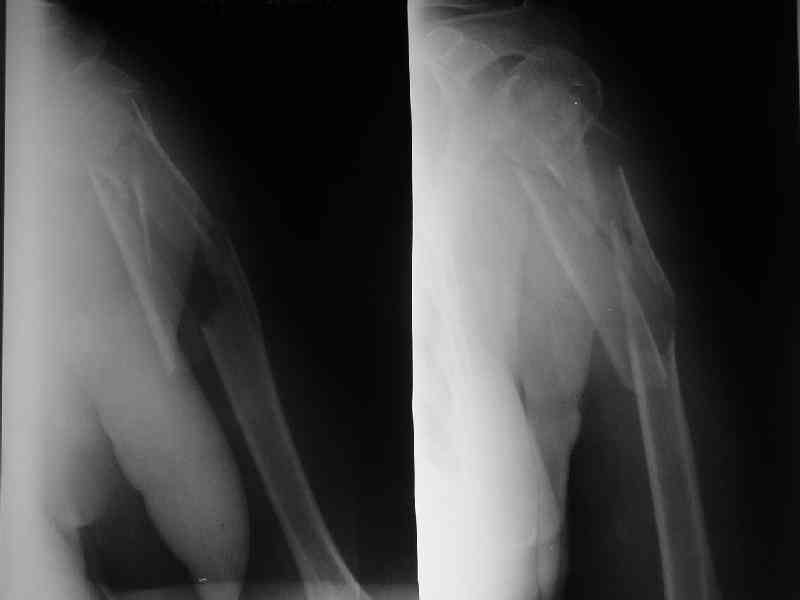

Re: Перелом плеча

Здесь нет необходимости в серкляже. Вмешиваться на промежуточных отломках приходится, если есть угроза перфорации кожи, или промежуточный отломок попал в фасцию, как пуговица в петлю. В приложении сегментарный оскольчатый перелом плеча в проксимальном отделе, фиксированный больщеберцовым стержнем. Как видите, обошлось без серкляжа. Функция полная.